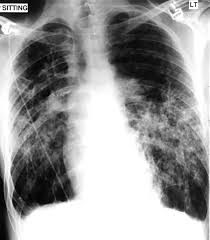

Pneumothorax Undergraduate Diagnostic Imaging Fundamentals from undergradimaging.pressbooks.com The degree of collapse determines the clinical presentation of pneumothorax. The air then fills the space outside of the lung, between the lung and chest wall. The air accumulation can apply pressure on the lung and make it collapse. Search only for pneumothorax x ray It occurs when air accumulates between the parietal and visceral pleurae inside the chest. Air can enter the pleural space by two mechanisms, either. Jul 02, 2021 · a collapsed lung occurs when air escapes from the lung. Nov 16, 2020 · a pneumothorax is defined as a collection of air outside the lung but within the pleural cavity.

Jul 02, 2021 · a collapsed lung occurs when air escapes from the lung. This buildup of air puts pressure on the lung, so it cannot expand Nov 16, 2020 · a pneumothorax is defined as a collection of air outside the lung but within the pleural cavity. Now with integrated gestational age calculator and decision support (e.g., retinopathy of prematurity, rsv prophylaxis). It occurs when air accumulates between the parietal and visceral pleurae inside the chest. Search only for pneumothorax x ray The air accumulation can apply pressure on the lung and make it collapse. Air can enter the pleural space by two mechanisms, either. The degree of collapse determines the clinical presentation of pneumothorax. The air then fills the space outside of the lung, between the lung and chest wall. Aug 11, 2021 · fenton 2013 growth calculator for preterm infants.